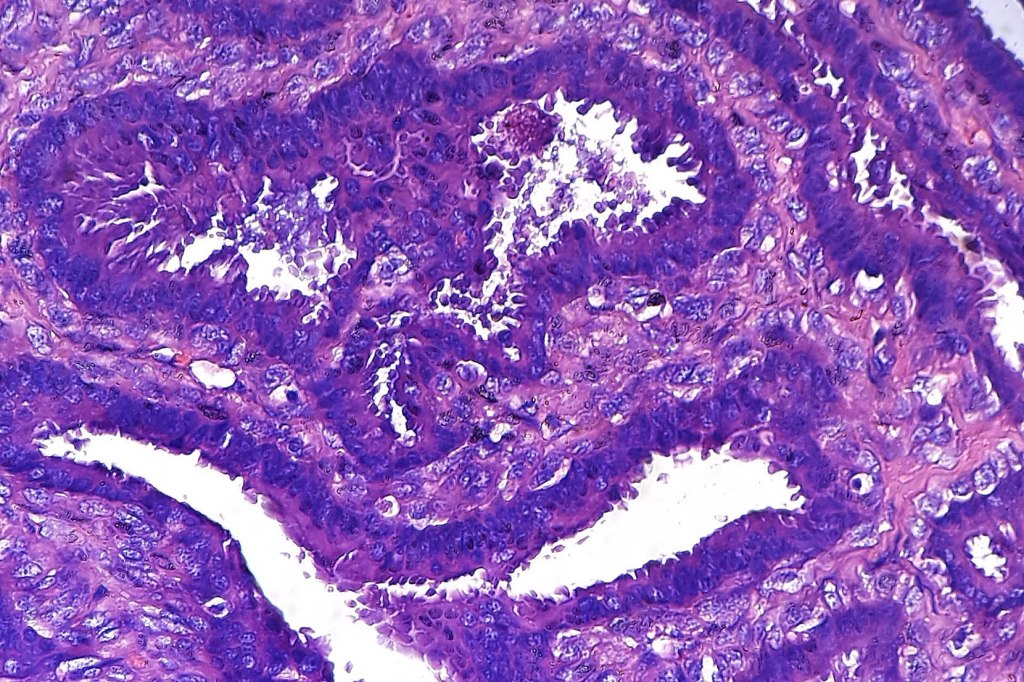

•Papillae lined by myoepithelial cells with overlying epithelial cells with eosinophilic cytoplasm showing decapitation secretion

•Cribriform pattern sometimes evident